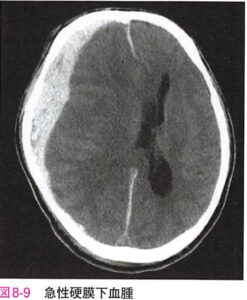

| 急性硬膜下血腫 | 脳表の架橋動脈や脳実質から出血し、硬膜下に血腫をつくる。CTで硬膜とくも膜の間に三日月状の高吸収が特徴。![]() |

急性硬膜下血腫 Acute subdural hematoma

| 病態 | 頭部外傷により脳表の静脈(複合型)>架橋V(単純型)が破綻し、硬膜下に血腫が生じた病態。乳幼児では強く頭を揺さぶられて架橋Vが破綻するshaken baby syndromeがある。![]() ![]() |

| 症状 | ①外傷直後の意識障害、もし意識があれば頭蓋内圧亢進症状(頭痛など) |

| 検査 | 【画像検査】 頭部CT:硬膜下に沿った三日月型の高吸収域 |

| 治療 | 緊急開頭して開頭血腫除去+出血源止血 |